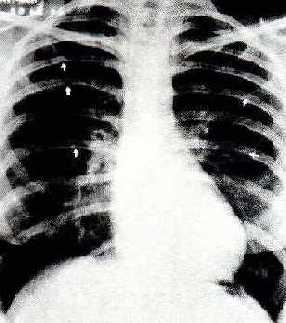

ESCAVACIONES DE LAS COSTILLAS EN LA RADIOGRAFIA DEL T�RAX.

La existencia de escavaciones o peque�as semilunas en el borde inferior de las costilla de forma bilateral es una signo patonogm�nico.